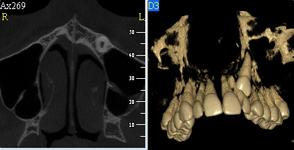

Jedná se o plánovací program, který využívá dat získaných při vyšetření pomocí přístroje New Tom. Tento program umožňuje tříprostorovou počítačovou simulaci při plánování pozic implantátů.

Součástí programu je i databáze, ve které mohou být uloženy všechny typy implantátů od všech výrobců, včetně jejich délek, průměrů i tvarů.

Lékař si vytvoří všechny typy zobrazení potřebných pro naplánování – tedy 2D snímky (panoramatický), příčné řezy i 3D model.

Vidí zde i důležité anatomické útvary – čelistní dutinu, průběh nervu atd. Po proměření množství kosti – šířky i výšky vybere z databáze vhodný typ implantátu a umístí ho do požadované lokality.

Ihned vidí jeho pozici ve všech 3 rovinách a na všech snímcích i 3D modelu. Může upravovat podle potřeby jeho pozici, sklon atd.

Tento program umožňuje tříprostorovou počítačovou simulaci při plánování pozic implantátů. Součástí programu je i databáze, ve které mohou být uloženy všechny typy implantátů od všech výrobců, včetně jejich délek, průměrů i tvarů.

Lékař si vytvoří všechny typy zobrazení potřebných pro naplánování – tedy 2D snímky (panoramatický), příčné řezy i 3D model.

Vidí zde i důležité anatomické útvary – čelistní dutinu, průběh nervu atd. Po proměření množství kosti – šířky i výšky vybere z databáze vhodný typ implantátu a umístí ho do požadované lokality. Ihned vidí jeho pozici ve všech 3 rovinách a na

všech snímcích i 3D modelu. Může upravovat podle potřeby jeho pozici, sklon atd.